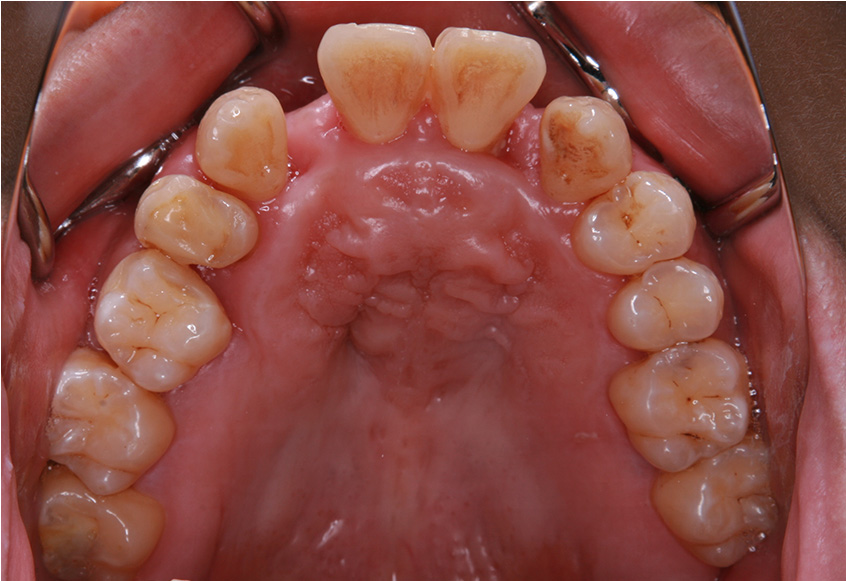

6ヵ月経過すると、矯正治療を終了し、前歯に被せ物の治療を行いました。

最初のお口の中 2025/3/22

被せ物装着

当院では、歯並びが気になる人に対して、矯正治療を行っています。また今回の症例のようにワイヤーを用いた治療からマウスピース矯正治療も行っておりますので、スタッフにお声かけください。

| 矯正装置 | 矯正ブラケットとワイヤー |

| 治療内容 | 上顎側切歯を2本抜歯した後、上顎の歯にブラケットを装着し、ワイヤー、矯正用ゴムで歯の移動を行いました。その後、被せ物の治療を行って治療を終了しています。 |